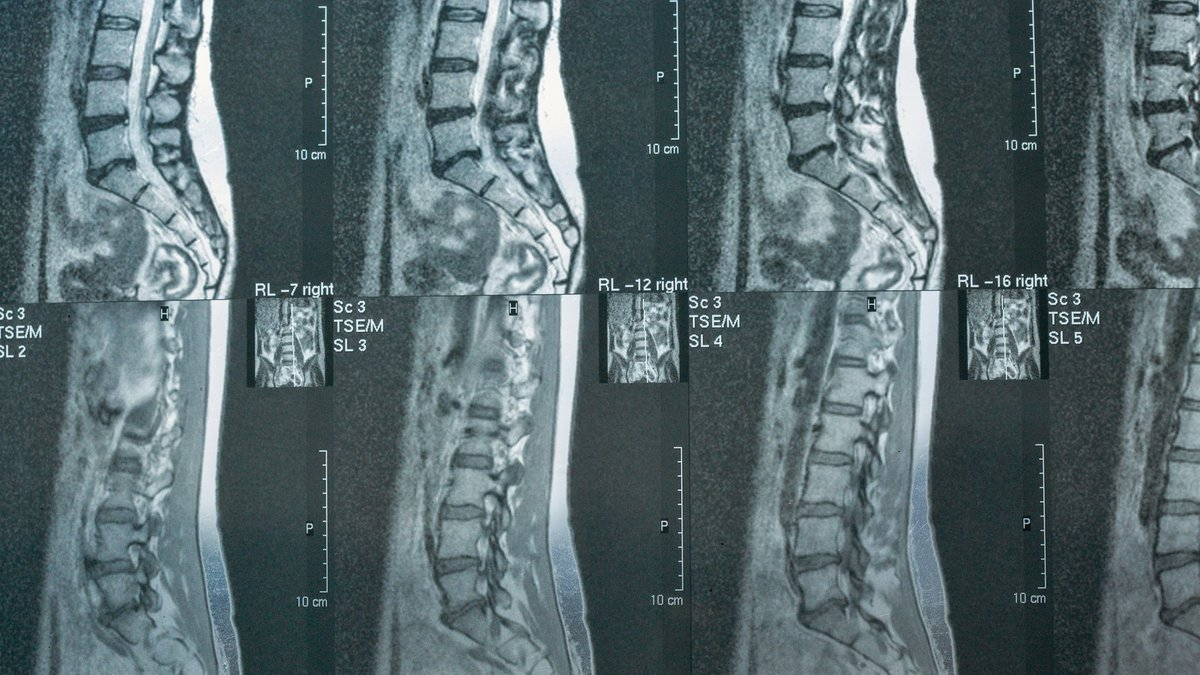

Ежегодно в мире регистрируется до 1 миллиона новых случаев травм спинного мозга, а более 10 миллионов человек живут с их последствиями. Повреждение этого ключевого «кабеля», связывающего мозг с телом, часто приводит к параличу и нарушению жизненно важных функций. Основная проблема в том, что нервные клетки взрослого человека практически не восстанавливаются, а в зоне травмы образуется рубцовая ткань, мешающая заживлению.